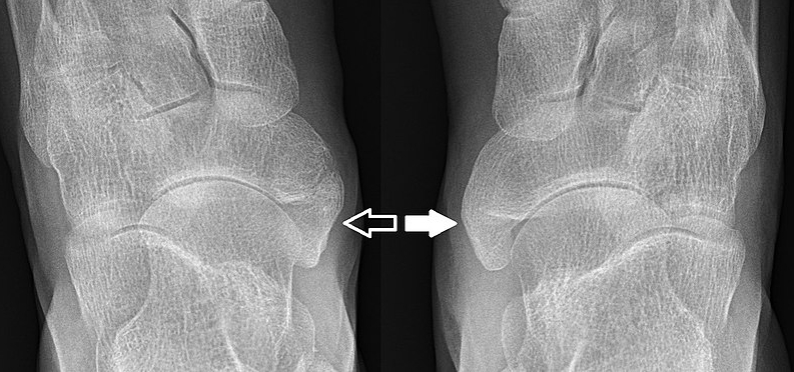

부주상골증후군이 의심된다면 발 전문가인 정형외과 전문의와 상담해야 할 때입니다. 정형외과 전문의는 발을 면밀히 검사하고 엑스레이를 통해 뼈를 자세히 살펴볼 수도 있습니다.